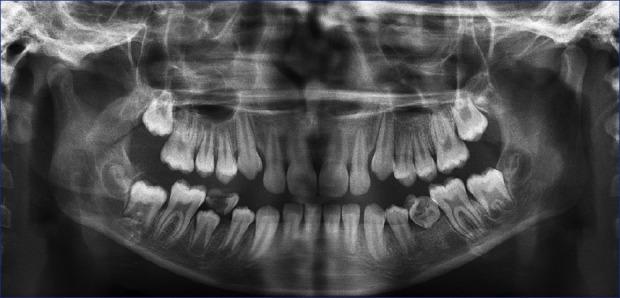

与下沉乳牙及额外前磨牙相关的前磨牙先天缺失:一例罕见病例报告。

Agenesis of premolar associated with submerged primary molar and a supernumerary premolar: An unusual case report.

The combination of submerged primary molar, agenesis of permanent successor with a supernumerary in the same place is very rare. The purpose of this article is to report a case of submerged mandibular left second primary molar with supernumerary tooth in the same region along with agenesis of second premolar in an 11-year-old girl, its possible etiological factors, and a brief discussion on treatment options.

摘要

下颌乳磨牙下沉、恒牙胚缺失且在同一位置有额外牙的情况非常罕见。本文旨在报告一例11岁女孩下颌左侧第二乳磨牙下沉,同一区域有额外牙且第二前磨牙胚缺失的病例、其可能的病因,并对治疗方案进行简要讨论。